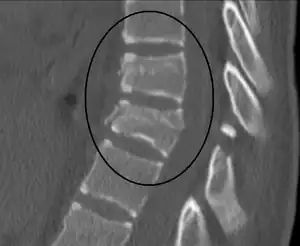

A flexion-distraction fracture of T10 and fracture of T9 due to a seatbelt during an MVC.

A CT scan of the chest, abdomen, and pelvis is recommended as part of the diagnostic work-up to detect any potential abdominal injuries.[9][8] MRI may also be useful.[8] The fracture is often unstable.[1]